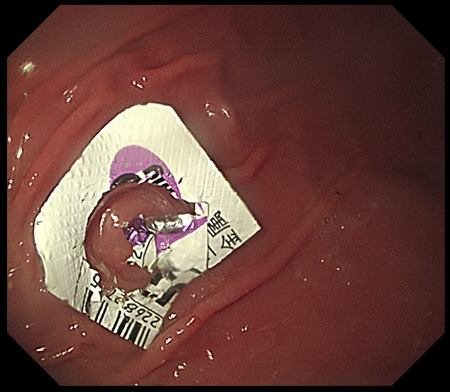

解答 解説 ある物 を誤飲したとして来院した80歳代女性 実践 画像

解答 解説 ある物 を誤飲したとして来院した80歳代女性 実践 画像

解答 解説 ある物 を誤飲したとして来院した80歳代女性 実践 画像

I M A Radiographer Radiotechnologist 私は放射線技師 ブログ

犬の誤飲によるptpシートを内視鏡で摘出除去 石川台どうぶつ病院